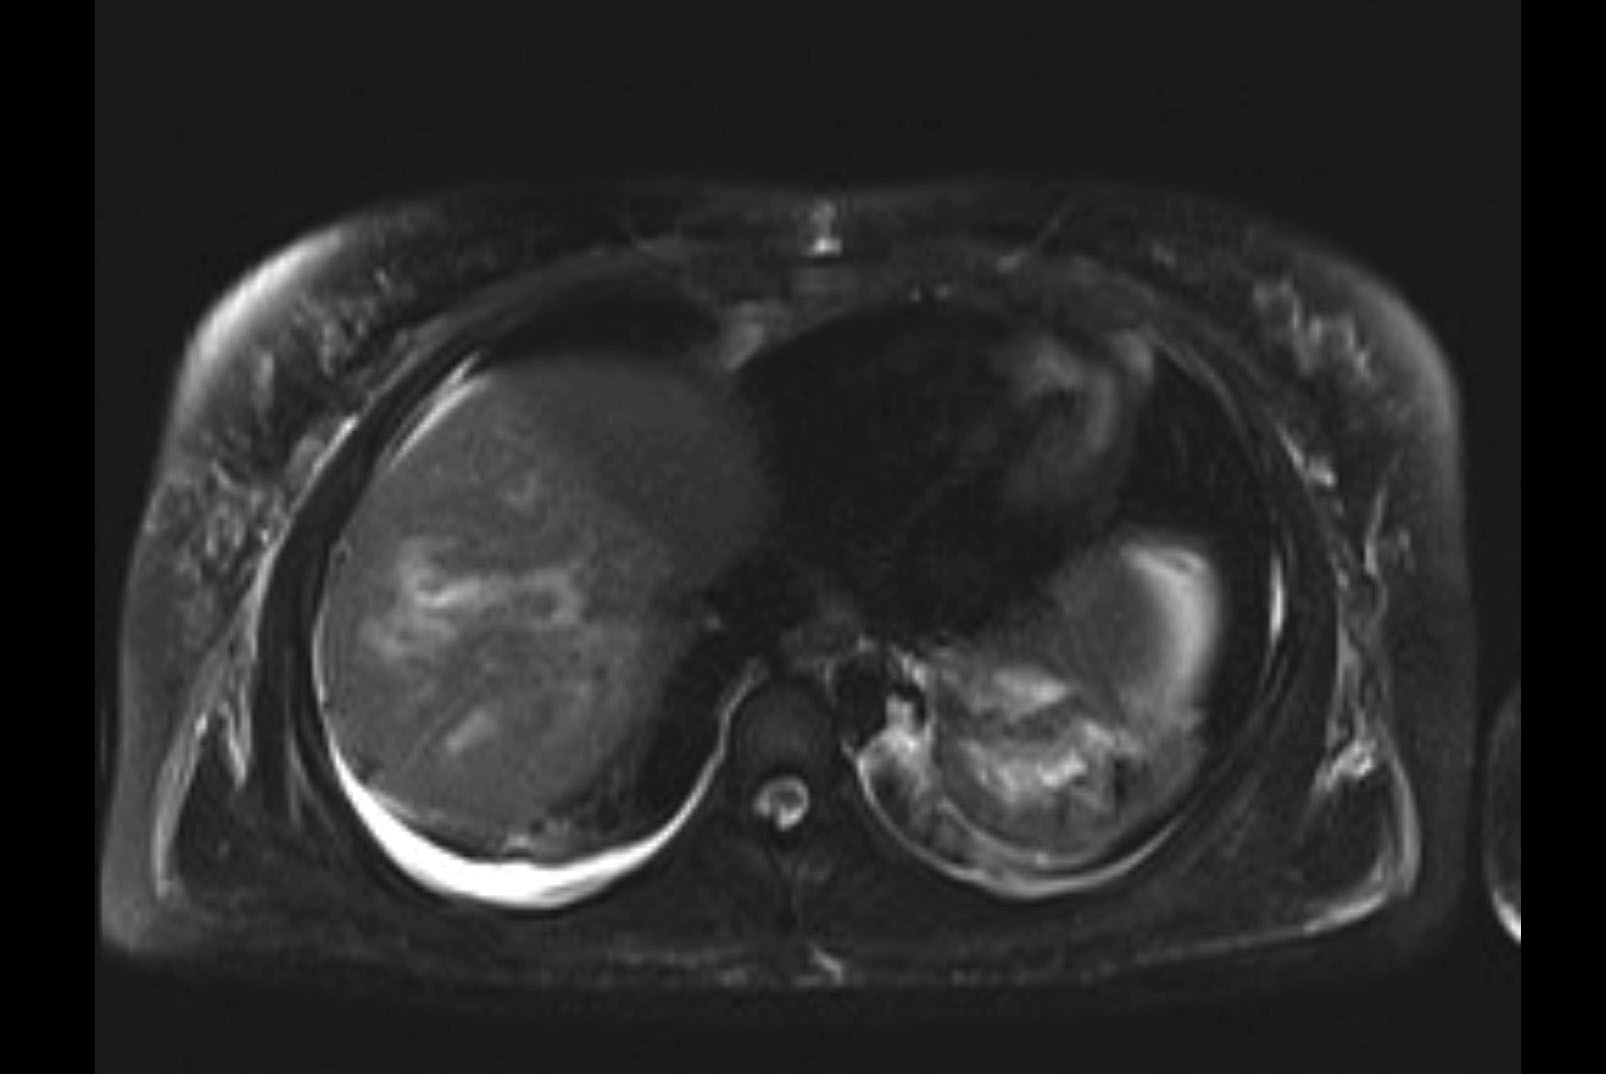

Imaging Analysis

Look through the patient's CT scan to identify any areas of concern for the necessary procedure.

MRI T1

Based on initial findings, which issue(s) would you be most concerned about?